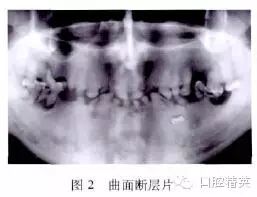

曲面断层片显示多数牙髓腔和根管闭锁,43,7421 12根尖周有较大阴影;2,7 457牙槽骨吸收至根尖;2,1 145牙根短;45牙根下方可见埋藏牙1颗(图2)。其余牙齿检查未见明显异常。询问家族病史,该患者自述其父亲及父系亲属的牙齿均与其类似。